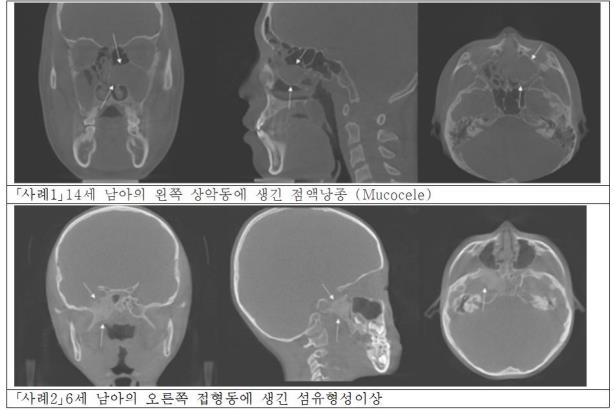

실제 치과용 엑스레이 영상 검사를 통해 14세 남아의 왼쪽 위턱뼈 인근에 생긴 점액낭종을 찾았고, 6세 남아의 부비동 가장 안쪽에 있는 접형동에 생긴 섬유 형성 이상도 진단이 가능했다.